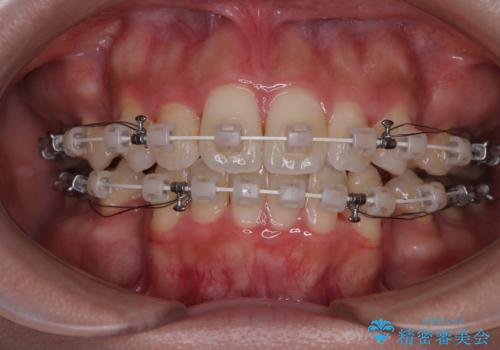

- 審美装置

- 1年10ヶ月

上下左右第一小臼歯4本を抜歯し、ワイヤー装置にて口元を引っ込めるよう矯正治療を行うこととしました。